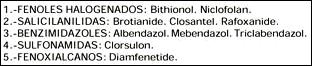

Las nuevos fasciolicidas, mencionadas en la tabla 4 en su mayoría son de uso veterinario, y no han sido aprobados en humanos a excepción de bithionol y praziquantel. El closantel y otros salicilanilidas interfieren con el metabolismo energético; triclabendazol interactúa con el citoesqueleto microtubular; diamfenetide bloquea la síntesis de proteínas del parásito y bithionol inhibe la fosforilación oxidativa y por consiguiente bloquea la síntesis de adenosin trifosfato. Alguno de ellos poseen efectos combinados por si solos. Sin embargo, existe la necesidad de desarrollar compuestos con alto grado de actividad contra estados inmaduros o intrahepáticos de Fasciola que eviten la patología asociada a la migración a través del parénquima o la via biliar. Este papel podría ser desempeñado por diamfenetide, clorsulon y triclabendazol (25). En nuestra paciente usamos exitosamente triclabendazol a dosis de 10 mg/Kg por dos días. La tasa de curación es de 79.2% con dosis única y de 100% con la segunda dosis (23).

Tabla 4. Nuevos fasciolicidas

La drogorresistencia no es un problema mayor al momento actual, pero ello no implica una conducta complaciente, se requiere constante vigilancia y monitoreo estricto para poder evitarla. Sin embargo, ya se han identificado resistencia a un número de fasciolicidas tanto in vitro como in vivo. Se sabe que triclabendazol a 10 mg/Kg reduce su eficacia contra fasciola de 2 semanas de vida de 98 a 60%. En Australia, triclabendazol usada en ovejas a 10 mg/Kg fue ineficaz contra Fasciola de 2, 4, 6 y 12 semanas de vida; y que a dosis de 20, 45 y 67 mg/Kg fue ineficaz contra Fasciola de 4 y 6 semanas, es más, a dosis de 100 mg/Kg su eficacia se redujo a menos del 80% contra Fasciola de 6 semanas de vida.

El uso extendido de la monoterapia no es deseable ya que puede desarrollar resistencia contra varias drogas químicamente no relacionadas, esto es resistencia cruzada. Cuando se sospecha o la resistencia ha sido establecida debe implementarse un programa con drogas alternativas. Una estrategia es el uso combinado de drogas.

Recientemente en Australia, el éxito de combinaciones sinergísticas de drogas de diferentes grupos químicos previenen la resistencia y se han usado en casos de Fasciola probadamente resistentes. Triclabendazol - Clorsulon o Triclabendazol - Luxabendazol (un nuevo benzimidazol de espectro ampliado) alcanzan alta eficacia contra cepas de Fasciola de 6 semanas de edad a dosis menores de las usualmente recomendadas individualmente. También han mostrado fuerte efecto sinergístico las combinaciones Closantel (7.5 mg/Kg) - Triclabendazol, Closantel - Clorsulon y Closantel - Luxabendazol; no así las combinaciones Closantel - Albendazol ni Closantel - Fenbendazol.